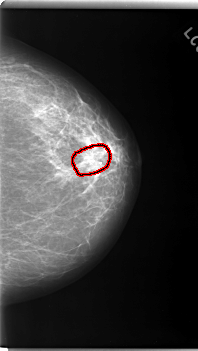

FILE: C_0170_1.LEFT_CC.OVERLAY

TOTAL_ABNORMALITIES 1

ABNORMALITY 1

LESION_TYPE MASS SHAPE ARCHITECTURAL_DISTORTION MARGINS SPICULATED

ASSESSMENT 5

SUBTLETY 5

PATHOLOGY MALIGNANT

TOTAL_OUTLINES 1

BOUNDARY